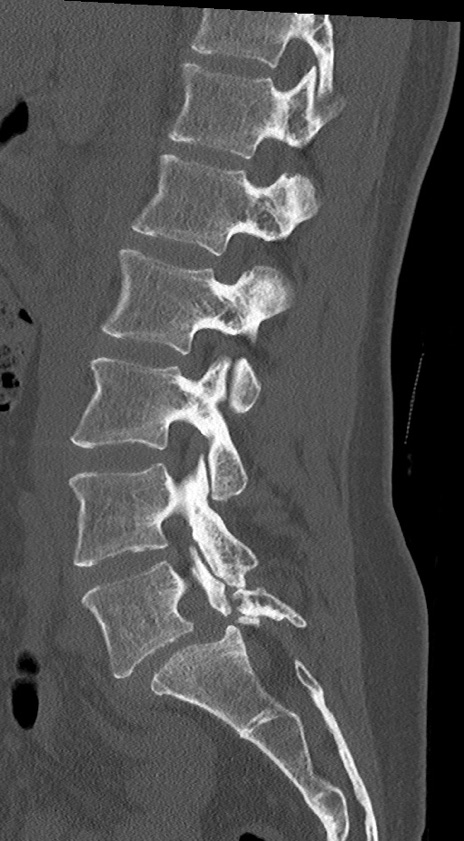

【整形】TIPS症例4 腰椎CT(矢状断像)

腰椎CT